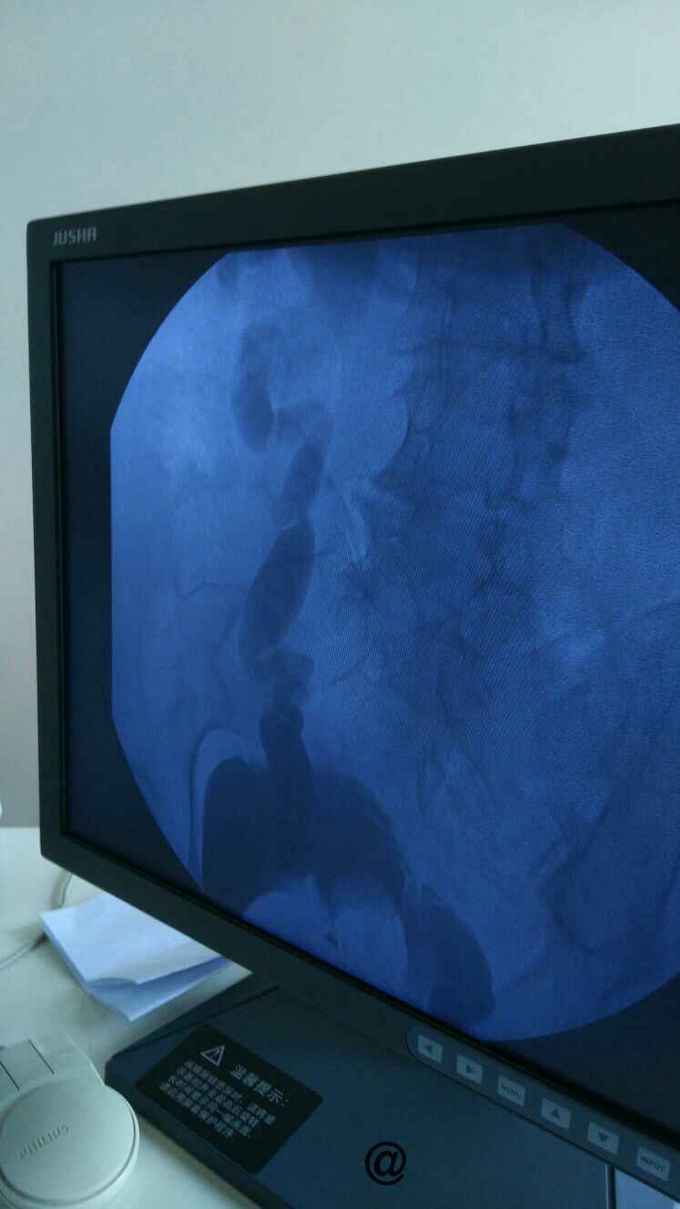

查膀胱镜发现后尿道狭窄,无法进入膀胱。 尿道造影:尿道狭窄,输尿管逆流。嘱咐病人排尿时,膀胱内尿液减少,进入输尿管,肾盂。 肾功能正常。

诊断:尿道狭窄,输尿管逆流 治疗:输尿管镜下探查,见尿道狭窄,膀胱内景清晰,广泛房小梁形成,右侧膀胱后壁可见广口凹陷,输尿管镜置入,可向上探查,实为输尿管,管腔宽大,输尿管镜进出自如,未见占位病变,向膀胱内置入导丝,沿着导丝留置导尿管扩张尿道。